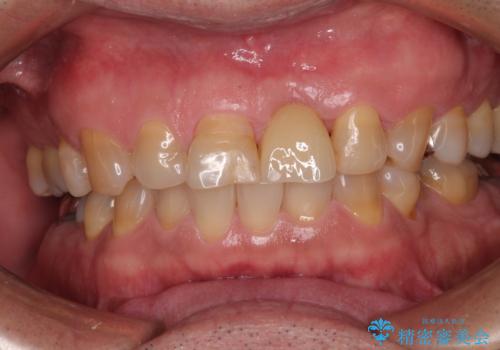

歯茎に溝が 大きく欠損した前歯のインプラント補綴治療

- 歯が朽ちてしまい、歯茎に大きな溝ができていることを気にして来院された患者様です。

インプラント治療を希望されておりましたが、軟組織の欠損が非常に大きいため、骨の回復を待ちながら歯肉の形態を整えていくこととしました。